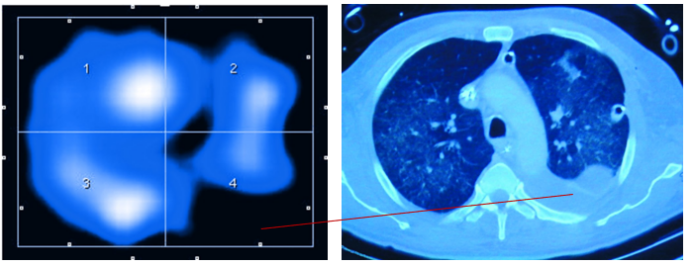

CT和EIT在应用中各具优缺点,但也有一定的互补性(表1,图2,视频1)

图片

2  CT解剖成像显示含气组织

视频1  EIT功能性呈像:显示气体进出变化的区域

EIT通过不同分区方式可将肺部分为多个感兴趣区(ROI): 一种是纵向划分, 包括ROI 1腹外侧、ROI 2腹内侧、ROI 3背内侧和ROI 4背外侧; 另一种是象限划分, 包含ROI 1右上区、ROI 2左上区、ROI 3右下区和ROI 4左下区。